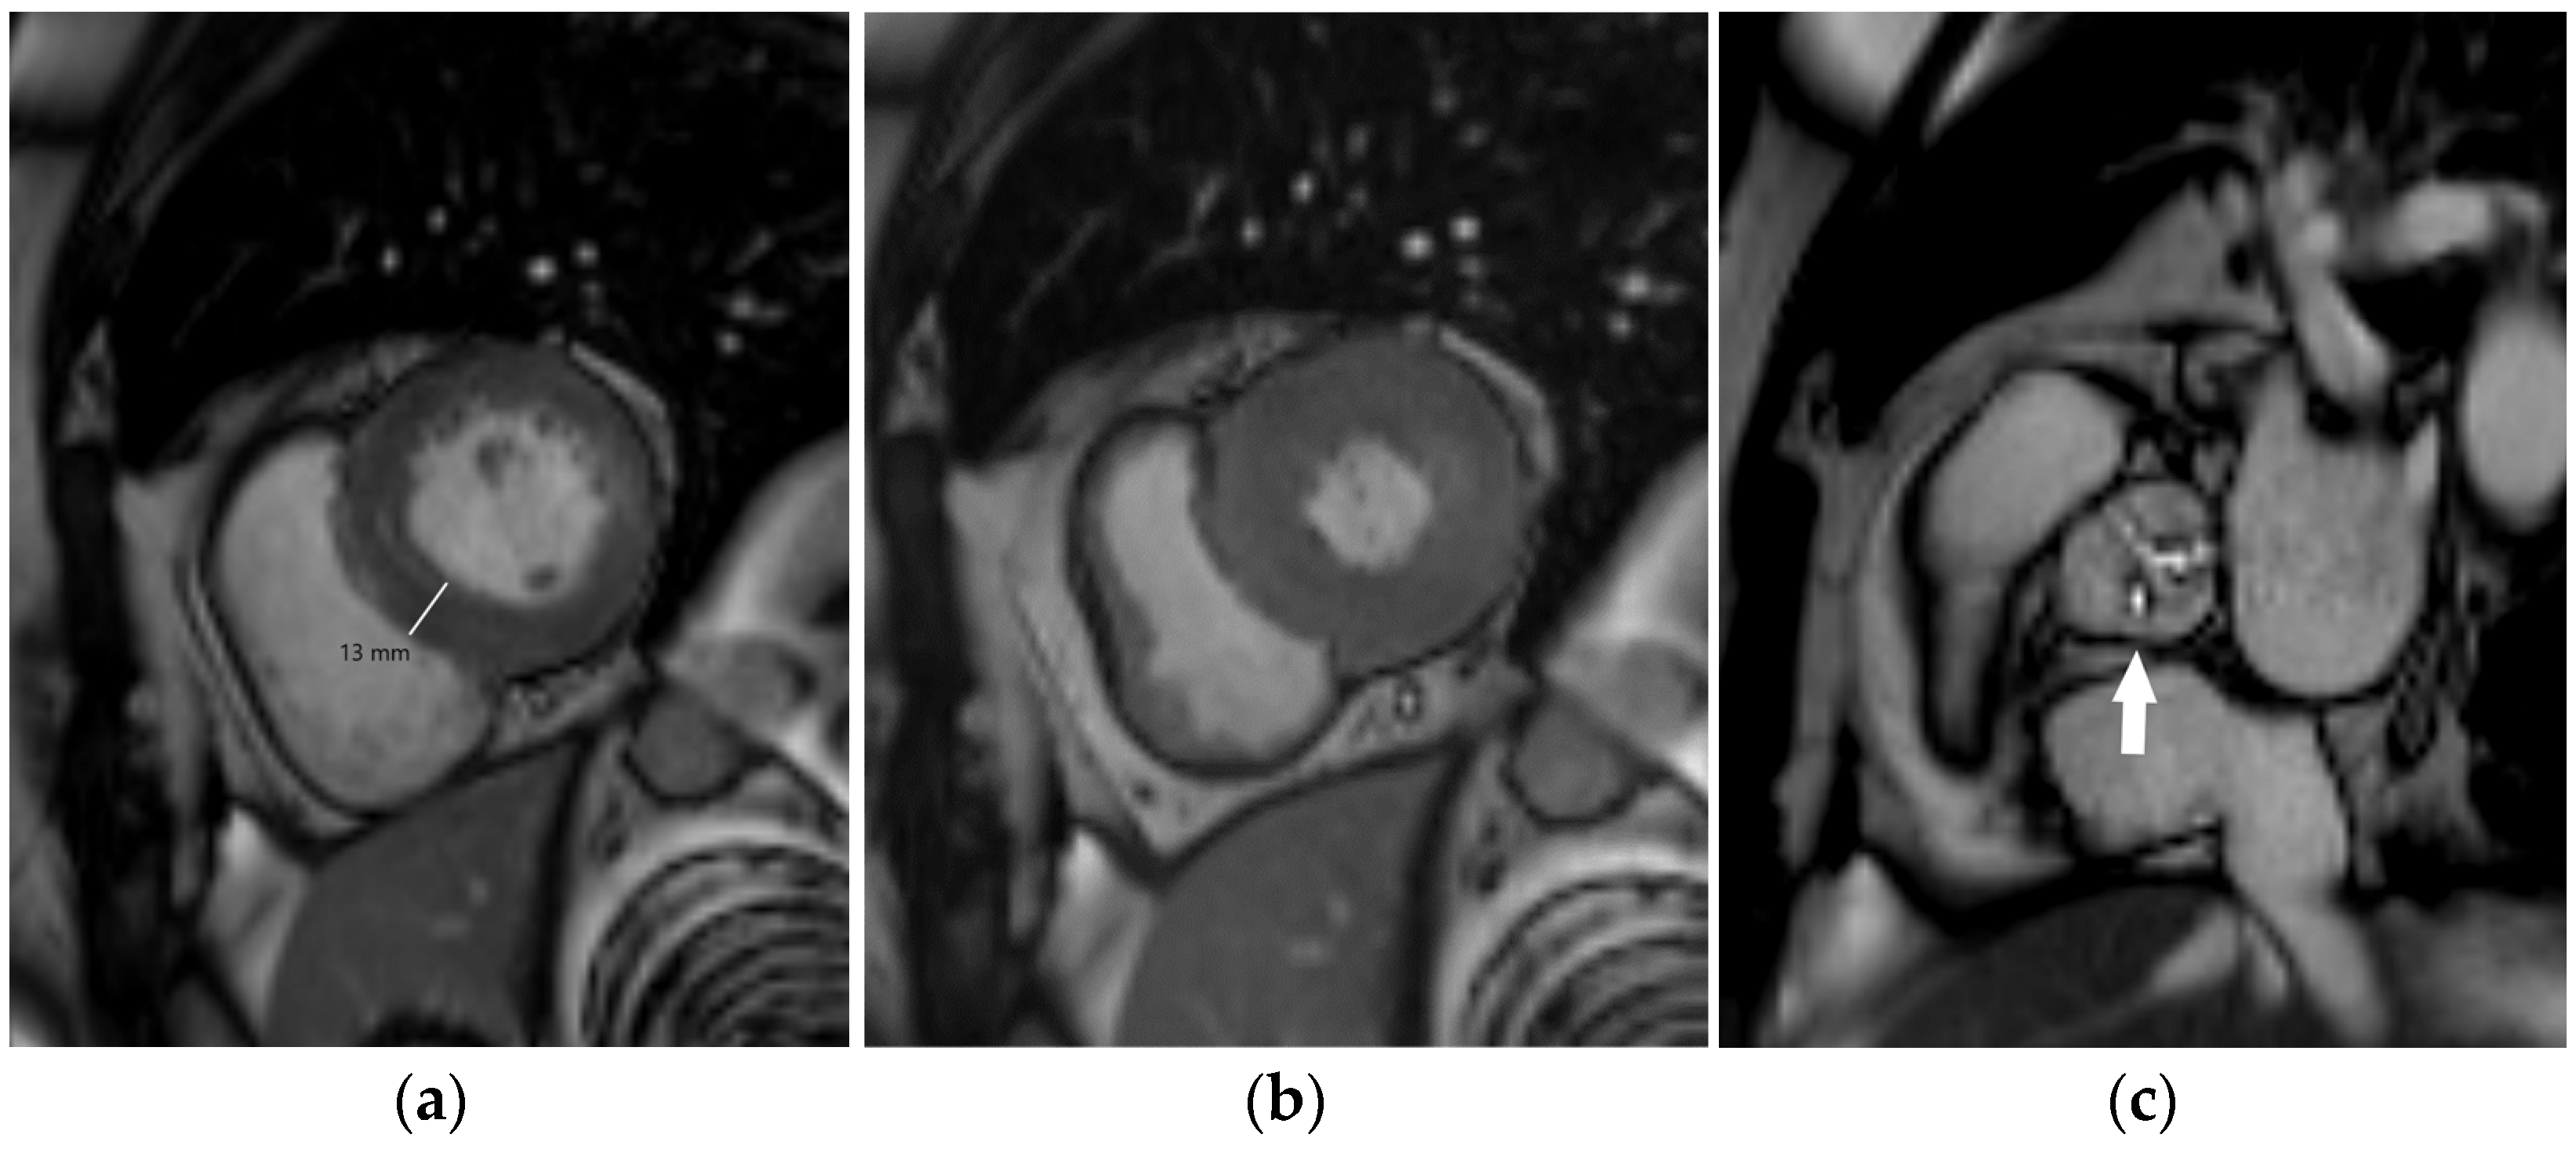

5.3. Magnetic Resonance Imaging

| Cardiac aging | |

| Myocardial hypertrophy | Increased left ventricular myocardial thickness and mass |

| Myocardial fibrosis | MRI tissue characterization required: prolonged myocardial T1 relaxation time, increased myocardial extracellular volume, late gadolinium enhancement |

| Valvular degeneration | Cusp thickening, stiffening, and calcification with reduced mobility |

| Diastolic dysfunction | Abnormal myocardial relaxation with impaired left ventricular filling |

| Coronary artery disease | CT: coronary artery calcification, coronary artery plaques with or without high-risk features, coronary artery stenosis |

| MRI: myocardial ischemia (stress testing), regional wall motion abnormalities (cine imaging), ischemic pattern of late gadolinium enhancement |

| Magnetic resonance imaging | Cardiac morphology and function Aortic morphology and stiffness (pulse wave velocity, aortic strain, and distensibility) | Imaging modality of choice for advanced assessment of cardiac morphology and function Non-invasive myocardial ischemia testing (stress test) Commonly used for follow-up of aortic diseases (especially in children and younger individuals) | Non-invasive myocardial tissue characterization Image acquisition in any desired plane The gold standard for assessment of myocardial mass, ventricular volumes, and ejection fraction | High costs Limited availability Long-lasting examinations Contraindications (ferromagnetic foreign bodies, non-conditional cardiac implantable electronic devices) |